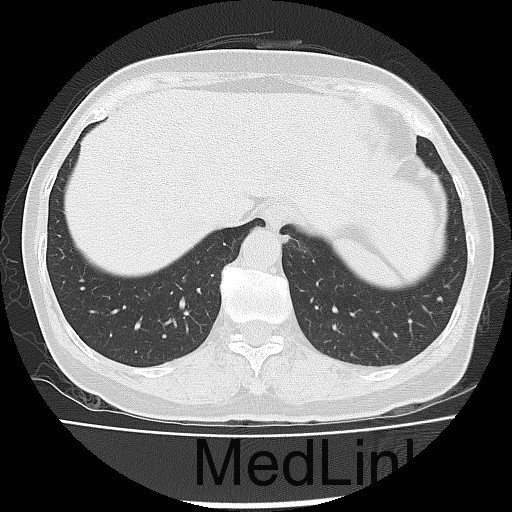

诊断:甲状腺恶性肿瘤(术后);手术后甲状腺功能减退。 治疗:入院时甲状腺球蛋白>455pmol/L,甲状腺素2.793uIU/ml,根据病情于2014-6-3予大剂量碘-131 100mCi清甲治疗;2014年6月全身碘扫示:全身多发异常摄碘组织,考虑甲状腺癌术后双侧甲状腺组织及锥状叶残留并全身多发骨转移。2014年9月胸部CT示:1、双肺多发转移瘤,并胸骨转移;胸1、8、10、腰1椎体内多发结节灶,考虑转移瘤可能性大。2、右肺中叶内侧段、双肺下叶散在慢性炎症。2014年12月全身碘扫:1.全身多处异常摄碘组织,考虑多发骨转移瘤。又于2014年12月复查甲状腺球蛋白抗体90.400U/mL,促甲状腺素6.914uIU/ml。遂于2014-12-22口服250mCi大剂量放射性碘-131。治疗后全身碘扫复查结果提示:2.左肺下叶摄碘组织,不排除转移瘤,建议进一步检查。与2014.6.6检查相比,颈部甲状腺部位放射性浓集灶消失,余病灶放射性浓集程度较前稍降低。

患者又于2015年10月胸部CT复查,结果提示:1、甲癌术后改变;双肺多发转移瘤,大部分病灶较前缩小,左肺下叶病灶较前增多,部分较前增大;胸骨转移;胸1、8、10、腰1椎体内多发结节灶,基本同前,考虑转移瘤可能性大。2、右肺中叶内侧段、左肺上叶舌段及双肺下叶散在慢性炎症。